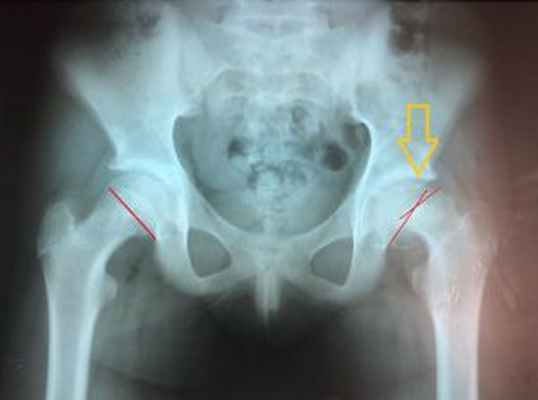

Поскольку вылечить запущенную стадию смещения трудно, ранняя диагностика эпифизеолиза головки бедренной кости является жизненно важной. Проводят передне-задний и латеральный – в положении лягушачьих ножек – рентген обоих бедер. Рентген выявляет расширение эпифизарных линий или очевидное заднее и нижнее смещение головки бедренной кости. Чтобы определить смещение, на рентгеновском снимке на верхней границе шейки бедра наносятся линии Клейна. Головка бедренной кости будет находиться ниже линии Клейна на пораженной стороне, в то время как на здоровой стороне значительная часть головки бедренной кости будет расположена выше линии Клейна.

Поражение головки бедра диагностируется травматологами-ортопедами на основании жалоб, результатов объективного обследования и визуализационных методик. Основным методом обследования является рентгенография тазобедренного сустава. Процедура выполняется в 2 проекциях, наиболее информативна боковая проекция. Изменения зависят от стадии заболевания.

Сначала ростковый хрящ на рентгеновских снимках расширяется, шейка становится слоисто-пятнистой из-за чередования участков остеосклероза и остеопороза. Затем обнаруживается прогрессирующее смещение головки, после этого просматривается линия перелома. На заключительной стадии выявляются признаки консолидации перелома, ремоделирование шейки бедра, сужение суставной щели.